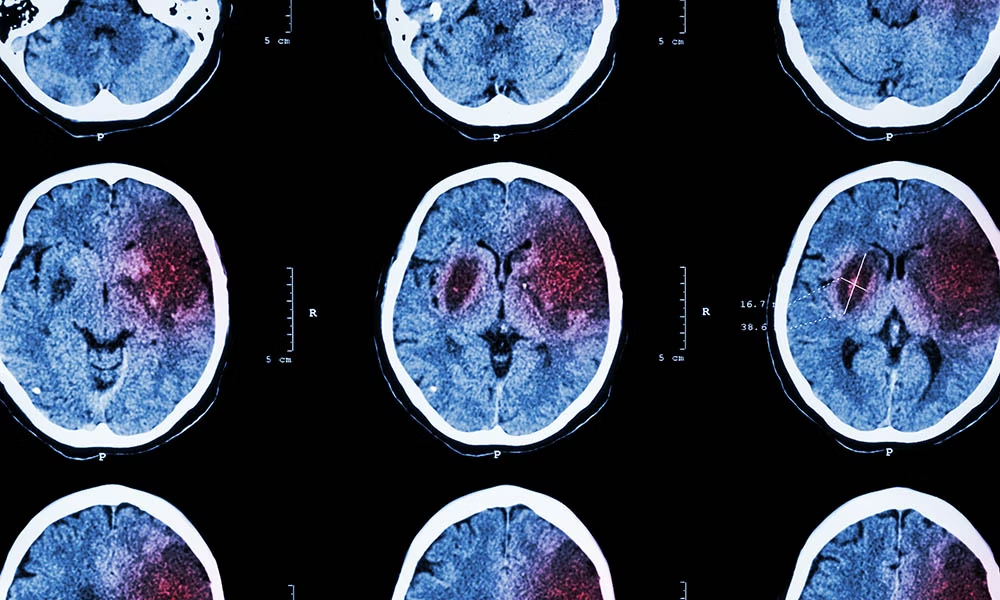

為了確保有針對性的治療,有必要確定患者是否患有血流量減少或腦出血。這通常通過成像技術來完成,例如大腦的計算機斷層掃描 (CT) 和/或磁共振成像 (MRI)。

腦梗塞(缺血)

腦出血(出血性中風)

腦出血涉及血液流入周圍的腦組織。由此產生的壓力可能會對未受影響的大腦區域造成額外的損害。這種腦內或腦外出血可能是由高血壓(高血壓)、凝血障礙、血管炎癥(血管炎)、腫瘤或血液稀釋劑(抗凝劑)不當的藥物治療引起的。

腦出血

中風會破壞大腦的血液供應(由于血流量減少或腦出血)。除臨床神經學檢查外,還通過影像技術(CT、MRI)進行診斷。